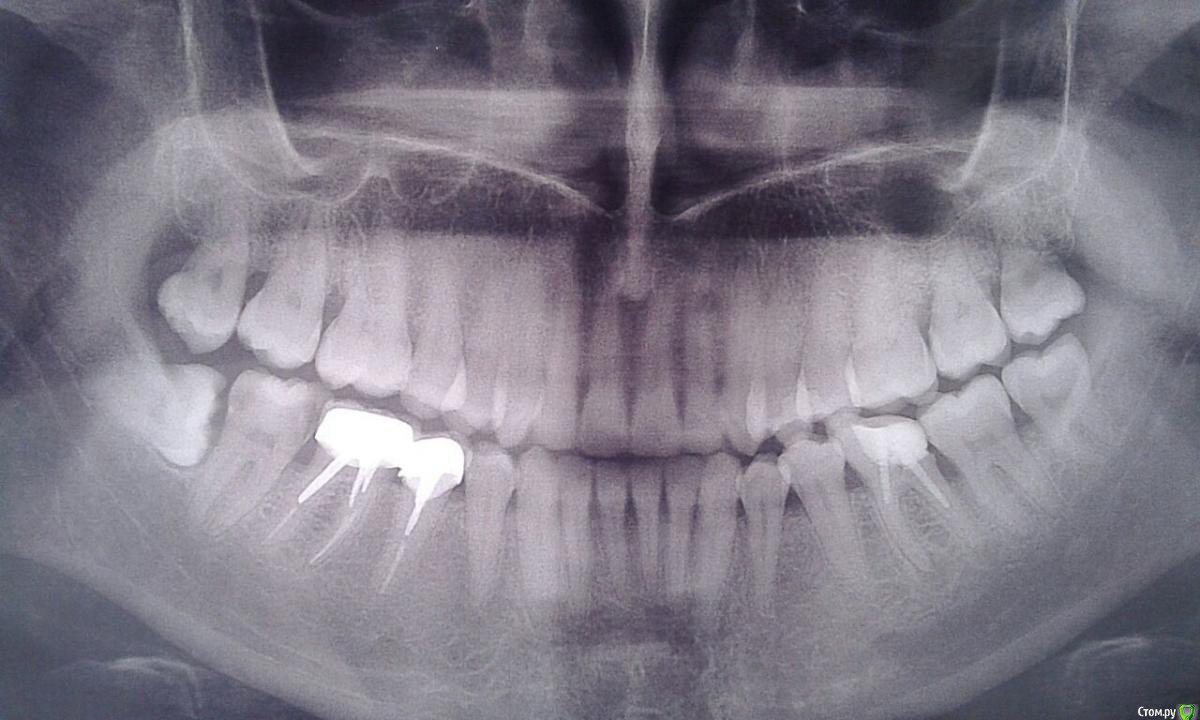

Carolina-84 Опубликовано 8 сентября, 2016 Поделиться Опубликовано 8 сентября, 2016 (изменено) Прошу оценить ситуацию объективно. В частной клинике, где делаю зубы постоянно, по результатам панорамного снимка врачи, за отсутствием челюстно-лицевого хирурга в штате, отказались браться и перенаправили в муниципальную поликлинику, с тем, чтобы хирург дал направление в Моники. Зуб залегает в теле кости челюсти, расположение не правильное, частично выглядывает из десны (прорезался давно и зуб по всей видимости сформированный) и лежит на лицевом нерве (понятно теперь откуда были непонятные симптомы недавно - нервный тик вокруг глаза и онемение правой стороны лица).После осмотра в городской стоматологии заведующим хирургического отделения, врач направление не дал, сказал будет делать сам. На мои вопросы: есть ли достойное оборудование, материалы и опыт работы - ответил: есть. Сделают все бесплатно.Я в сомнениях. Параллельно записалась в г.Зеленоград на платную консультацию.На сколько сложны подобные операции и делаются они в стоматологическом кабинете или в хирургическом? Почему не спросил КТ, уверенность в своих силах или халатность? Прилагаю снимок. Можно ли по такому снимку получить достоверную картину сложности предстоящей операции или все-таки делать КТ? Идти к муниципальному хирургу или в платную клинику, на сколько сложна моя ситуация? Изменено 8 сентября, 2016 пользователем Carolina-84 Ссылка на комментарий

diesel87 Опубликовано 8 сентября, 2016 Поделиться Опубликовано 8 сентября, 2016 Здравствуйте, сложности особой в удалении нет, такое можно и в частной клинике сделать. Удаляйте сразу и верхнюю восьмерку, потому как она не функционирует и уже выдвинулась вниз. Нижний зуб лежит не на лицевом нерве, а рядом с нижнечелюстным, тик справа вряд ли можно с этим связать. Удаление предпологает распил зуба на части и удаление его по частям. После может быть отек, не полное открывание рта и боль при глотании. 1 Ссылка на комментарий